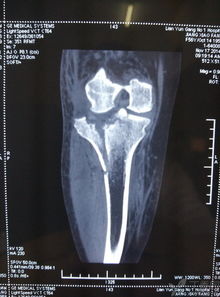

胫骨平台是位于胫骨上端的一个平台,与股骨的髁部形成膝关节。胫骨平台骨折是指胫骨平台部位发生的骨折,可能是由于直接撞击、跌倒或扭伤等原因引起。根据骨折的严重程度和位置,可分为多种类型,如单纯骨折、粉碎性骨折等。

并非所有胫骨平台骨折都适合保守治疗。以下情况可以考虑采用保守治疗:

胫骨平台关节面塌陷小于2mm